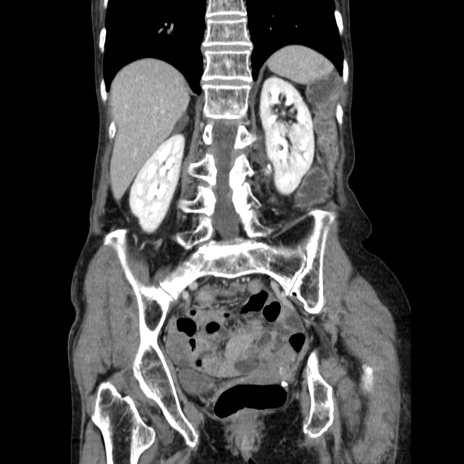

症例25(冠状断像)

【症例】80歳代女性

【主訴】胸のつかえ感

【現病歴】約9時間前に食後から胸のつかえた感じあり、嘔吐あり、来院。

【既往歴】胃癌(全摘)、胆摘、虫垂炎

【身体所見】心窩部に圧痛あり、反跳痛なし。

【データ】WBC 5700、CRP 0.05